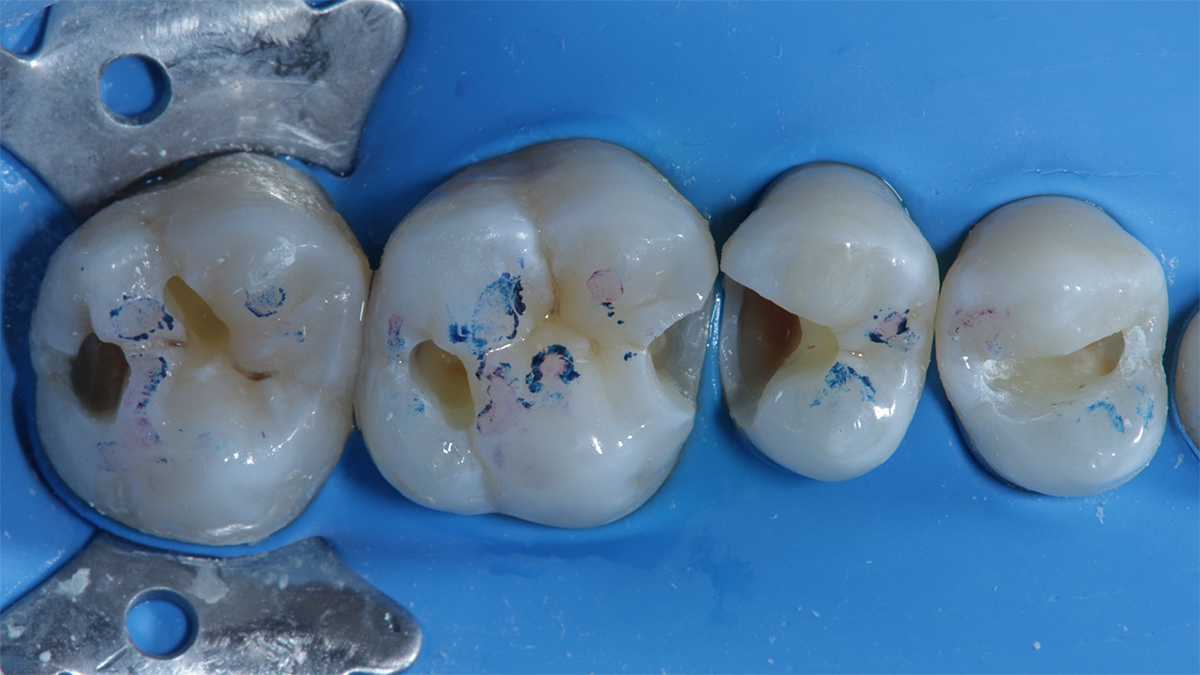

La corretta selezione dei cunei interdentali in odontoiatria restaurativa è fondamentale per la precisione ed il successo a lungo termine del restauro. Infatti, i cunei sono strumenti essenziali ne

La corretta selezione dei cunei interdentali in odontoiatria restaurativa è fondamentale per la precisione ed il successo a lungo termine del restauro. Infatti, i cunei sono strumenti essenziali nel garantire un corretto adattamento della matrice al gradino cervicale, nel ridurre la formazione di debordi, nel promuovere un’emergenza anatomica e nel contribuire alla creazione di una perfetta area di contatto.

I cunei assolvono a diverse importanti funzioni:

- stabilizzano la matrice sezionale e ne garantiscono l'adattamento cervicale: fondamentale per evitare la formazione di debordi ed un'emergenza il quanto più anatomica possibile.

- Creano una distrazione ortodontica temporanea, sfruttando l'elasticità del legamento parodontale. Questo permette di costruire un'area di contatto competente e non lassa.

Al contrario, dispositivi moderni come 3D Fusion™, Strata-G™ e Wedge Wands™, sono progettati per offrire una combinazione di forza di separazione calibrata, adattamento tridimensionale ed ergonomia di inserimento. I materiali sintetici utilizzati non si deformano in modo imprevedibile e mantengono la loro forma e funzione per tutta la durata del restauro. La presenza di superfici anatomiche flessibili, come nel caso del sistema 3D Fusion™ e Strata-G™, permette un ottimale adattamento della matrice al gradino cervicale riducendo significativamente il rischio di debordi e migliora la qualità del punto di contatto. Le sistematiche 3D Fusion™ e Strata-G™ grazie alla loro morfologia sigillano in modo adattivo e tridimensionale anche in presenza di concavità radicolari. Questa tipologia di cunei trova indicazione nella quasi totalità della casistica clinica di tutti i giorni. In particolar modo risulta più semplice il restauro in presenza di gradini cervicali concavi, grazie al design e alla struttura siliconica flessibile.